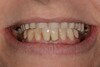

Le patient présente des malpositions dentaires importantes altérant l’esthétique de son sourire.

Le cliché panoramique révèle l’état radiculaire des dents naturelles résiduelles.

La décision est prise d’extraire les dents résiduelles et d’implanter dans le même temps 5 implants à la mandibule et 6 implants au maxillaire. En 7 jours, l’esthétique du sourire du patient a changé radicalement. Les deux bridges provisoires seront portés pendant 6 mois.

Résultat final pour ces deux bridges à armature titane et finition résine. Les dents en résine fixent les colorations alimentaires plus vite que les dents en zircone mais leur coût est moindre. L’ombrage bleu sur les deux incisives est dû au papier bleu qui sert au réglage occlusal.